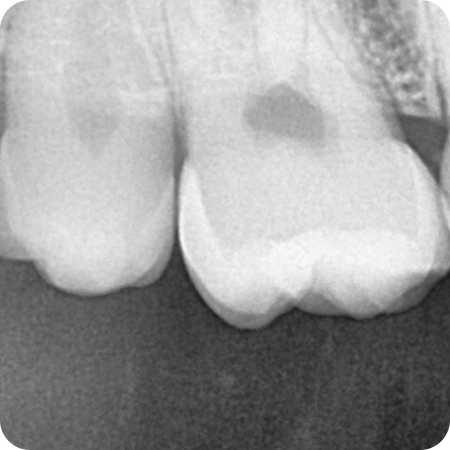

타이밍을 놓치지 않고

필요한 치료만

충치 치료

레진 치료

충치 범위가 크지 않은 경우 치아 색상과

물성이 비슷한 레진이라는 재료를 이용하여

충치 부위를 제거한 후 충전 하는 치료 방식입니다.

인레이 치료

충치가 깊거나 넓은 경우 금, 도재, 레진 등의

재료를 이용하여 기공소에서 제작 후

보철물을 부착하는 치료 방식입니다.

크라운 치료

신경치료 후 약해진 치아를 보호하거나

심하게 손상된 치아 전체를 지르코니아,

금 등의 재료로 감싸는 치료 방식입니다.